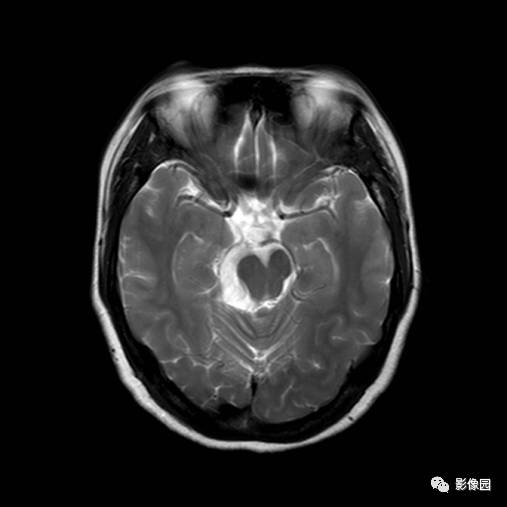

小脑发育不良性神经节细胞瘤的MRI诊断